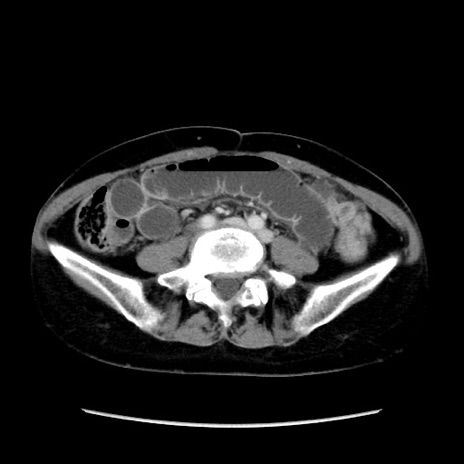

症例32(横断像)

【症例】40歳代 女性

【主訴】上腹部痛、嘔気・嘔吐

【現病歴】約9時間前頃から急に上腹部痛、嘔気、嘔吐が出現。改善しないため救急要請。

【既往歴】子宮頚癌(広汎子宮全摘術、放射線療法)、腸閉塞

【身体所見】腹部:平坦、軟、腸雑音亢進、上腹部を中心に腹部全体に圧痛あり。

【データ】WBC 8400、CRP 0.03